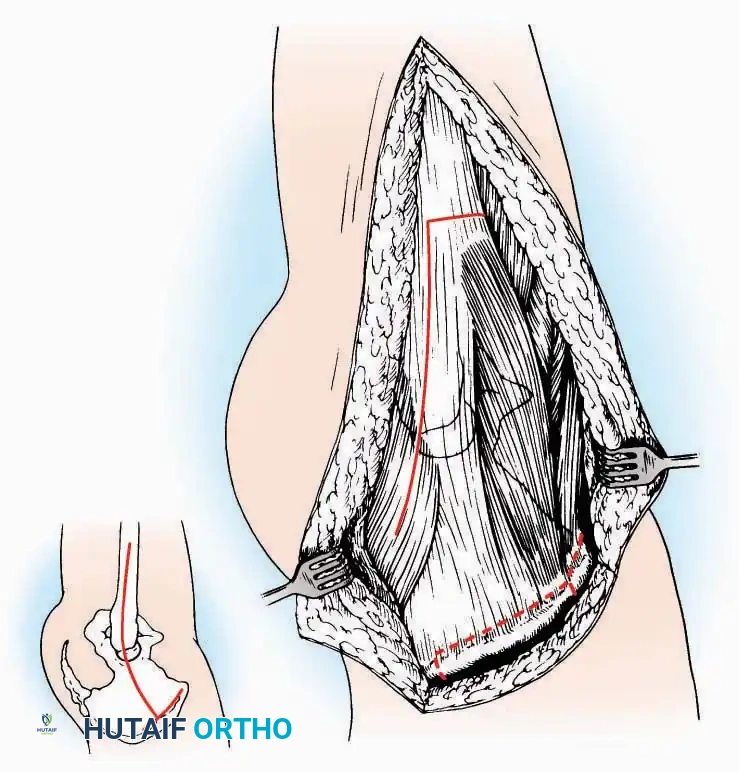

Lateral Approach (Extensile Lateral)

This is the workhorse approach for open reduction and internal fixation (ORIF) of displaced intra-articular calcaneal fractures.

Indications: ORIF of calcaneus fractures, lateral wall exostectomy, subtalar arthrodesis.

Positioning: Lateral decubitus with the operative leg up, or supine with a large bump under the ipsilateral hip to internally rotate the leg.

Surgical Technique:

* Incision: Begin the incision on the lateral margin of the Achilles tendon near its insertion. Extend it distally to a point 4 cm inferior and 2.5 cm anterior to the lateral malleolus. (For trauma, a classic L-shaped extensile incision is often used, dropping straight down anterior to the Achilles, then curving gently toward the base of the 5th metatarsal).

* Superficial Dissection: Divide the superficial and deep fasciae. It is imperative to create a "full-thickness" flap containing skin, subcutaneous fat, and periosteum to prevent flap necrosis.

* Nerve Protection: The sural nerve crosses the proximal and distal limbs of this approach. It must be identified and protected within the anterior flap.

* Deep Dissection: Isolate the peroneal tendons (longus and brevis). Incise and elevate the periosteum below the tendons to expose the lateral wall of the calcaneus.

* Tendon Management: If severe deformity or infection is present, the peroneal tendons may be divided via Z-plasty and repaired at the conclusion of the case, though this is rarely necessary in modern fracture care.